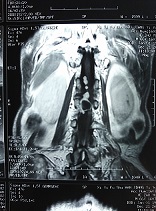

患者叶XX59岁男性,腰背部疼痛伴右侧腹股沟及臀部、大腿外侧放射痛3月余。半月前乘坐三轮摩托车后明显感觉疼痛加重,右下肢力量减弱,走路不稳,只能一直卧病在床。随后患者来我院检查。经我院骨科主治医师吴晓鸿的门诊细致检查,发现患者腰背部疼痛伴右下肢肌力减弱,通过CT、核磁等进一步检查,发现患者腰1—腰2椎管内巨大、多发肿瘤占位病变。

20161228日,在西安交大二附院王栋教授指导、协助下,吴晓鸿主治医师与李建栋副主任医师、王礼副主任医师及第五勇刚主治医师一起,顺利为该患者完成经后路全椎板减压、椎管内肿瘤切除、后路植骨内固定治疗。手术过程非常顺利,术后次日患者即感觉右下肢大腿及腹股沟疼痛症状消失。术后拍片复查见内固定稳定。减压、植骨效果良好。经过外二科护理团队的精心护理,患者现正在顺利恢复中。